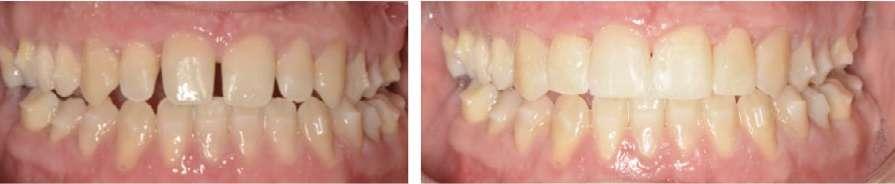

2. Análisis intraoral (Ilustración 2 y 3):

 Clase III molar y canina de Angle bilateral.

 Mordida abierta anterior > 3 mm.

 Compresión maxilar junto con mordida cruzada posterior bilateral.

 Línea media inferior desviada 2 mm hacia la derecha.

Ilustración 2. Fotografías intraorales iniciales de estudio.

Corrección vertical (Ilustración 7):

 Extrusión de incisivos superiores (1,7 mm) e inferiores (1,5 mm) con attachments de control radicular.

 Intrusión de molares mandibulares mediante turbo bites para facilitar el cierre de la mordida.

Como se puede apreciar en las imágenes adjuntas, la corrección vertical planificada se logró en su totalidad. En esta etapa, se colocaron carillas provisionales de composite de canino a canino en la arcada superior para mejorar la estética del paciente y compensar la discrepancia de Bolton (Ilustración 8). Para la corrección sagital se fabricó un nuevo juego de alineadores transparentes.

Corrección sagital (Ilustración 9):

 Corrección de la inclinación corono-distal de los premolares en el cuarto cuadrante mediante elásticos intermaxilares.

Ilustración 7. Fotografías iniciales, post-disyunción e intra-tratamiento tras el 1º set de alineadores Spark™ (corrección vertical).

Ilustración 9. Fotografías intraorales tras el 2º set de alineadores Spark™ (corrección sagital).

Tras 18 meses de tratamiento, se concluyó la fase ortodóncica y se colocaron las carillas de composite definitivas de canino a canino en la arcada maxilar, obteniendo los siguientes resultados:

1. Expansión maxilar efectiva junto con mejoría en la estética de la sonrisa (Ilustración 10):

 Se corrigió la mordida cruzada posterior bilateral disminuyendo los corredores bucales.

 La expansión obtenida fue > 5 mm, evidenciada en la tomografía post-tratamiento.

2. Corrección de la mordida abierta anterior (Ilustración 11):

 Extrusión controlada de los incisivos con alineadores y attachments.

 Reducción de la mordida abierta de 3 mm, logrando una sobremordida adecuada.

3. Mejora de la relación oclusal:

 Conversión de la relación molar y canina de Clase III a Clase I funcional.

 Centrado de las líneas medias.